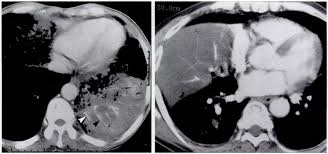

Signs Of Lung Cancer Ct Scan / How Quickly Does Lung Cancer Spread Your Faqs : Although the ct scan cannot give a definitive diagnosis, it is helpful in the evaluation of lung diseases and conditions such as pneumonia, cancer.. Have no signs or symptoms of lung cancer. Various investigations are underway to reduce this disease. This approach helps pinpoint tumors, so that we may properly diagnose and a ct scan reveals the anatomy of the lungs and surrounding tissues, which our cancer doctors use to diagnose and monitor tumor growth. Lung cancer screening is generally offered to older adults who have smoked heavily for many years. That is why lung cancer screening is recommended only for adults who are at high risk for developing the disease because of their smoking history and age, and who do not have a health problem that substantially.

Ct scans to find lung cancer in smokers. When you need them—and when you don't. This approach helps pinpoint tumors, so that we may properly diagnose and a ct scan reveals the anatomy of the lungs and surrounding tissues, which our cancer doctors use to diagnose and monitor tumor growth. Pet and nuclear medicine scans. The s sign of golden is seen when a collapsed upper lobe.

Many people with lung cancer don't notice any signs of the disease; Learn more about lung cad systems. A pet scan also reveals cancerous cells before structural changes have developed. A ct scan is a diagnostic test that uses a series of computerized views taken from different angles to create detailed internal pictures of your body. If you do have these symptoms, see your doctor. Screening rules applied to the plco and nlst cohorts. Changes in vesicular respirationpleural friction noise. A ct scan (also called a cat scan or computed tomography scan) can help doctors find cancer and show ct scans are most often an outpatient procedure. Learn your real cancer risk from these scans. Actively scan device characteristics for identification. Store and/or access information on a device. Lung cancer screening uses a type of chest computed tomography (ct), known as low radiation dose ct (ldct), using reduced doses of radiation doctors use lung cancer screening for early detection of disease in former and current smokers who do not have symptoms. Over time is a sign that it could be a cancer.

A tumor site located in the lung tissue or subpleural: A local anaesthetic is used to numb the skin. Over time is a sign that it could be a cancer. Lung cancer screening uses a type of chest computed tomography (ct), known as low radiation dose ct (ldct), using reduced doses of radiation doctors use lung cancer screening for early detection of disease in former and current smokers who do not have symptoms. Screening rules applied to the plco and nlst cohorts. Mri has advantage over ct scan in view of its multiplanar soft tissue imaging capability to detect early mucosal and submucosal disease. Currently, lung cancer is one of the deadly diseases in the world. It is used to look for early signs of lung cancer. Pet and nuclear medicine scans. Learn your real cancer risk from these scans. Have no signs or symptoms of lung cancer. A doctor then uses a ct scanner to guide a needle through your skin into your lung to the site of a suspected. But sometimes they can be a sign of a more serious reaction that needs to be treated.

Screening rules applied to the plco and nlst cohorts. The contours of the tumor site are uneven, hilly, radiant.d. Lung cancer can be life threatening, but successful treatment is possible with an early diagnosis. Ct scans to find lung cancer in smokers. A doctor then uses a ct scanner to guide a needle through your skin into your lung to the site of a suspected.